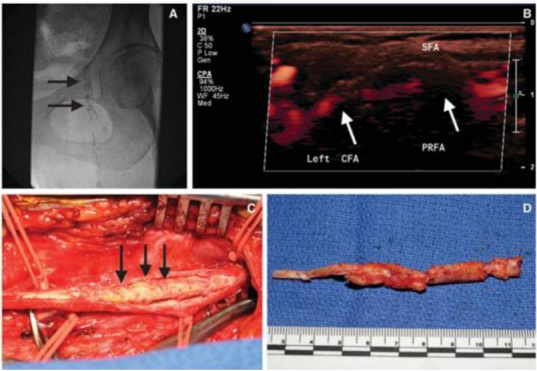

严重的钙化斑块——定向斑块旋切术

在血管斑块病变中,严重钙化斑块因质地坚硬、难以扩张,成为临床治疗的重点与难点。定向斑块旋切术凭借其精准靶向的技术特性,为这类复杂病变提供了高效、安全的治疗选择,成为破解严重钙化斑块困境的核心手段之一。

针对严重钙化斑块,可预扩后使用Hawk进行减容

长期严重钙化

长段严重钙化病变因钙化范围广、质地坚硬,常规扩张治疗易出现血管撕裂、夹层等并发症,且管腔开通效果不佳。定向斑块旋切术凭借 “精准切削、靶向清除” 的核心优势,成为这类复杂病变的优选治疗方案,为临床破解长段钙化难题提供了高效路径。